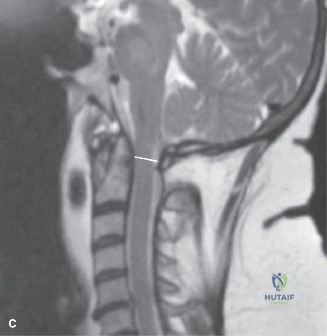

Pre-Operative Planning, Templating, and Patient Positioning

When surgical intervention becomes unavoidable, meticulous pre-operative planning is the cornerstone of a successful outcome. Advanced imaging is non-negotiable. An MRI with and without gadolinium contrast is the gold standard for defining the extent of the epidural abscess, the degree of neural compression, and the involvement of adjacent paraspinal musculature (e.g., psoas abscess). T1-weighted images typically show hypointense signals in the infected marrow, while T2-weighted and STIR sequences reveal hyperintense fluid and edema in the disc space and vertebral bodies. Gadolinium enhancement highlights the vascularized inflammatory phlegmon and the capsule of any abscesses.

In addition to MRI, a fine-cut computed tomography (CT) scan is essential for evaluating bony destruction. CT allows the surgeon to assess bone stock for pedicle screw purchase and to template the size of the interbody cages required for anterior column reconstruction. Upright standing radiographs (if the patient can tolerate them) or full-length supine films are necessary to evaluate global spinal alignment and regional kyphosis.